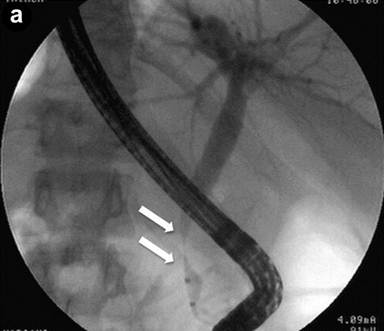

Patient#6: Diffuse form of autoimmune pancreatitis.

A 25-year-old man presented with jaundice, dilated bile ducts and an enlarged pancreatic gland at sonography; IgG4 levels were elevated (802 mg/dL). Endoscopic retrograde cholangiography (ERC) (Image 6a) showed stenosis of the distal common bile duct (arrows), and a stent was positioned. EUS linear scans (Image 6b) confirmed a substantially and diffusely enlarged pancreas, (arrows: pancreatic head), with echopoor echotexture and hyperechoic septa; the common bile duct, containing the stent, showed a three-layered, "sandwich-pattern" and thickening of the wall (arrowheads).